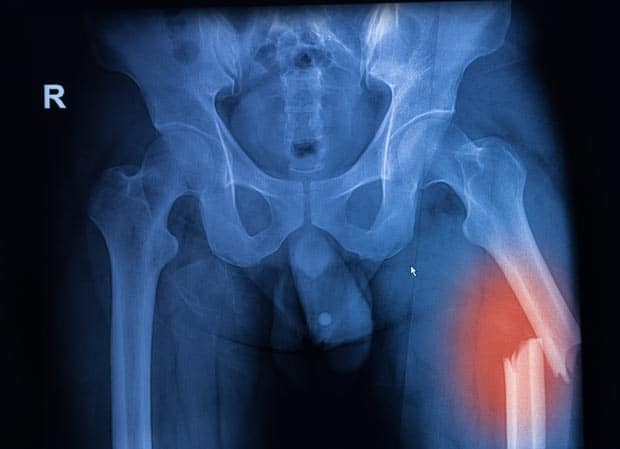

Травмы бедра и тазобедренного отдела

Бедренные кости и тазобедренный сустав обеспечивают все двигательные функции человека.

Стрессовый перелом бедренной кости

Это нарушение нормального восстановительного процесса костной ткани бедренной кости, вызванное чрезмерными нагрузками.

В начальный период боль возникает только при движениях бедра и ощущается в области паха и внутренней части бедра. При сохранении стрессовых условий болевой синдром усиливается и может наступить полный перелом кости.

Постоянные усиленные тренировки или резкое увеличение их интенсивности приводят к дисбалансу тонуса мышц бедра и создают повышенную нагрузку, которая провоцирует возникновение усталостного перелома.

Правильная система тренировок и постепенное увеличение их интенсивности помогают уменьшить риск такой травмы.